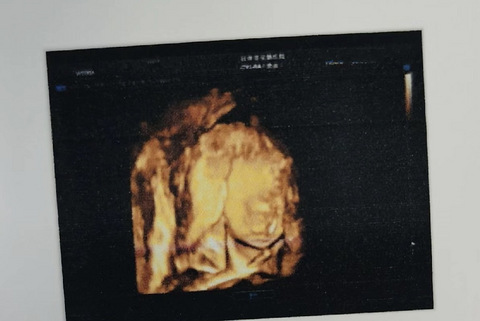

给你们看看花钱拍的彩超“一塌糊涂”,还没有免费彩超照得清楚

第一张是我产检的医院拍的,预约的10点到医院,大排畸做完了就差拍个脸了,可是宝宝不配合,一早上前后进了三次B超室,宝宝要么体位不好,要么用手遮着脸,医生说他好调皮,不知道是不是暗示我是男宝,中途各种巧克力,各种爬楼梯,一早上都没拍到脸,医生让我下午再去,下午去好不容易勉强拍了个嘴和下巴,其他的被脐带挡了 医生说没有唇裂,其他看不到,就这样打发我走了......